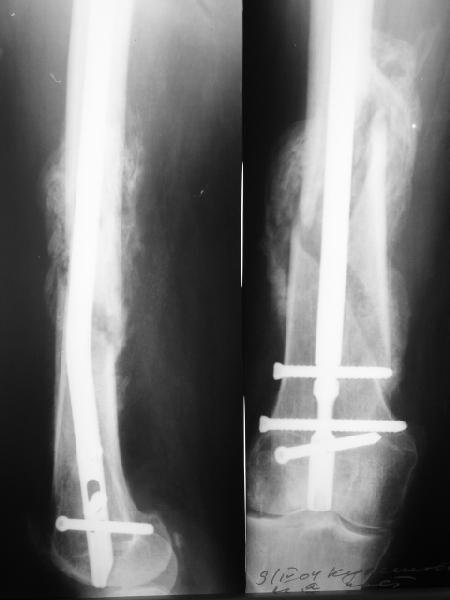

Результат операции блокирующего остеосинтеза многооскольчатого перелома бедра. Применены винты собственной конструкции.(моделирование спогиозного винта)

По прямой проекции неплохо. Что за стержень?

Антеградный остеосинтез при дистальных переломах бедра мы применяем давно, этот материал обобщен в канд. диссертации Александра Виноградского.

Предприятие ЦИТО выпускает доработанные нами гвозди, которые хорошо годятся для дистальных переломов, да и недороги. Можно вводть в дистальное овальное отверстие 3 винта, которые заклинивают друг друга.

Большеберцовые стержни отлично выполняют роль ретроградных бедренных. Конечно, которые не 9, а 12 мм в диаметре.

Примеры приложены.

И вообще мне кажется, что представленный ОС не допустим:1. стержень в суставе,2. неправильная длинна винтов, 3. ось конечности неправильная, 4. циркулярная гипсовая повязка после ОС?????

-2. неправильная длинна винтов,

и толщина тоже. При такой длине хочется помощнее.

Вполне прилично. Если в боковой проекции рекувации нет. Где кстати боковая, хочется спросить у постмейкера.

Если в боковой проекции все не менее достойно, и винты в отверстиях, это метод выбора.

Затем, что результаты как минимум не хуже, чем при использовании глубокоспециализированных DFN. Другое дело, что найти толстый тибиальный гвоздь больше 11м не всегда просто. В показаном примере он бы не подошел. Трочал бы сильнее из колена или при полном погружении отверстия пролетели бы проксимальнее перелома. Он показан больше для нижней трети, чем для области метафиза. Да и желательно чтобы винты толстые были, толще чем для тибии.

Приносим извенения за недостаток информации. Выкладываю все снимки. Стержень фирмы НПО ДЕОСТ(г.Пущино-на-оке)